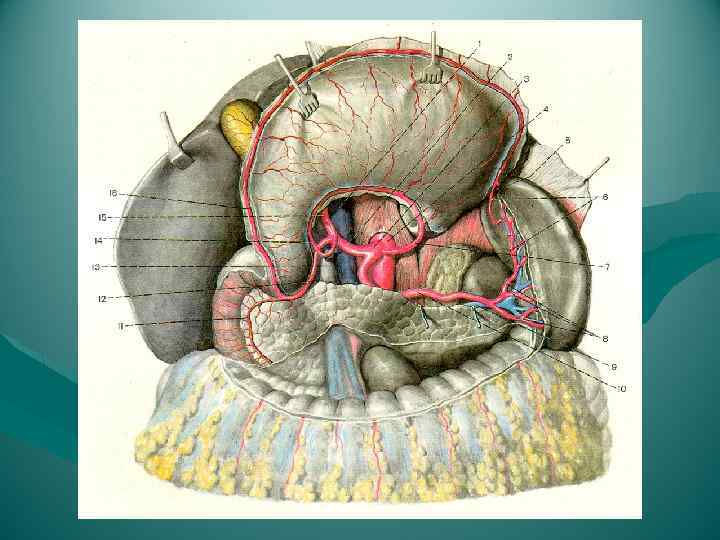

Кровоснабжение головки поджелудочной железы осуществляется из передней и задней артериальных дуг, образованных двумя верхними (из a. gastroduodenalis) и двумя нижними (от начального отдела a. mesenterica superior) панкреатодуоденальными артериями. От каждой из названных дуг в паренхиму головки отходит от 3 до 7 артерий. Тело и хвост поджелудочной железы снабжаются кровью из rr. pancreatici от селезеночной артерии. Отток венозной крови происходит непосредственно в воротную вену и ее главные притоки — vv. lienalis et mesenterica superior.

Кровоснабжение головки поджелудочной железы осуществляется из передней и задней артериальных дуг, образованных двумя верхними (из a. gastroduodenalis) и двумя нижними (от начального отдела a. mesenterica superior) панкреатодуоденальными артериями. От каждой из названных дуг в паренхиму головки отходит от 3 до 7 артерий. Тело и хвост поджелудочной железы снабжаются кровью из rr. pancreatici от селезеночной артерии. Отток венозной крови происходит непосредственно в воротную вену и ее главные притоки — vv. lienalis et mesenterica superior.

Взаимоотношение поджелудочной железы с двенадцатиперстной кишкой, общим желчным протоком, воротной и нижней полой венами, брюшной аортой и ее ветвями. 1 — v. cava inferior; 2 — aorta abdominalis; 3 — truncus coeliacus; 4 — a. gastrica sinistra; 5 — a. lienalis; 6 — v. lienalis; 7 — v. mesenterica inferior; 8 — a. mesenterica superior; 9 — v. mesenterica superior; 10 — caput pancreatis; 11 — duodenum; 12 — a. gastroduodenalis; 13 — a. hepatica communis; 14 — a. hepatica propria; 15 — ductus choledochus; 16 — a. gastrica dextra; 17 — v. portae; 18 — ductus cysticus; 19 — ductus hepaticus communis.

Взаимоотношение поджелудочной железы с двенадцатиперстной кишкой, общим желчным протоком, воротной и нижней полой венами, брюшной аортой и ее ветвями. 1 — v. cava inferior; 2 — aorta abdominalis; 3 — truncus coeliacus; 4 — a. gastrica sinistra; 5 — a. lienalis; 6 — v. lienalis; 7 — v. mesenterica inferior; 8 — a. mesenterica superior; 9 — v. mesenterica superior; 10 — caput pancreatis; 11 — duodenum; 12 — a. gastroduodenalis; 13 — a. hepatica communis; 14 — a. hepatica propria; 15 — ductus choledochus; 16 — a. gastrica dextra; 17 — v. portae; 18 — ductus cysticus; 19 — ductus hepaticus communis.